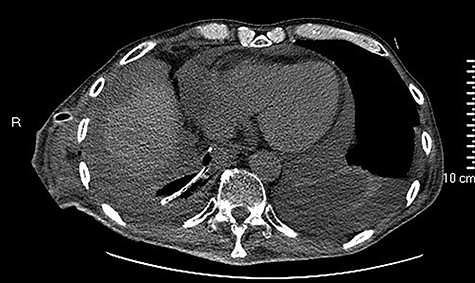

Intracavitary placement of E-VAC with prompt progressive improvement of the cavity size.

high PCR (291 mg/L) and the CT scan showed a right hydropneumothorax (Fig. 1). The first suspicion was an anastomotic leak and, in consideration of the hemodynamic instability and the severe septic state, the patient was submitted to emergency surgery. We performed a thoracoscopy with intraoperatively esophagogastroduodenoscopy which revealed a perforated prepyloric ulcer of the gastric tube. We therefore proceeded with accurate pleural toilette and closed the perforation with surgical stiches. At the end of the procedure, two thoracic drains and a naso-gastric tube with the distal end near the suture were placed. An additional naso-duodenum enteral feeding tube to ensure adequate nutrition was positioned. The patient was admitted in the Intensive Care Unit and supported with inotropic drugs, broad-spectrum antibiotics and proton pump inhibitor therapy. In the following days, the patient’s conditions improved allowing his extubation and his transfer to the surgical ward. Unfortunately, imaging and endoscopic check revealed a recurrent perforation. Considering the failure of the conservative approach, we decided to start the E-VAC Therapy on his 21st post-operative day (POD), using the Eso-SPONGE® System (B. Braun Surgical, S.A. Carretera De Terrassa, Rubi, Spain), firstly placed intraluminal because of the reduced size of the wall defect (Fig. 2). After three E-VAC replacements we did not observe any endoscopic or radiologic improvements. Moreover, on his 35th POD, due to a new impairment of vital signs, the patient underwent a second surgical treatment, with a new pleural toileting and another unsuccessful attempt of closing the conduit defect surgically. Considering the prolonged hospital stay, we placed a feeding jejunostomy. We proceeded with a new attempt of E-VAC, this time by placing it intracavitary (Fig. 3 and Fig. 4). The E-VAC was changed every 48–72 hours, reshaping the dimension of the sponge every time according to the size of the cavity. We observed a progressive reduction of the cavity size during the seriated endoscopic and CT evaluation. Considering the continuous improvement of patient’s clinical condition we discharged him after 84 days of hospitalization, with the E-VAC in place. The device replacement was carried on twice a week as an outpatient treatment, until its definitive removal (Fig. 5). The total duration of the therapy was 37 days with 13 E-VAC intracavitary interventions. Seven days after the device removal we performed an upper gastrointestinal X-Ray with oral contrast that showed no contrast medium leakage. The patient was therefore allowed to resume oral intake. At 6 months follow up the patient was in good clinical conditions; radiological test and endoscopy showed no abnormalities.